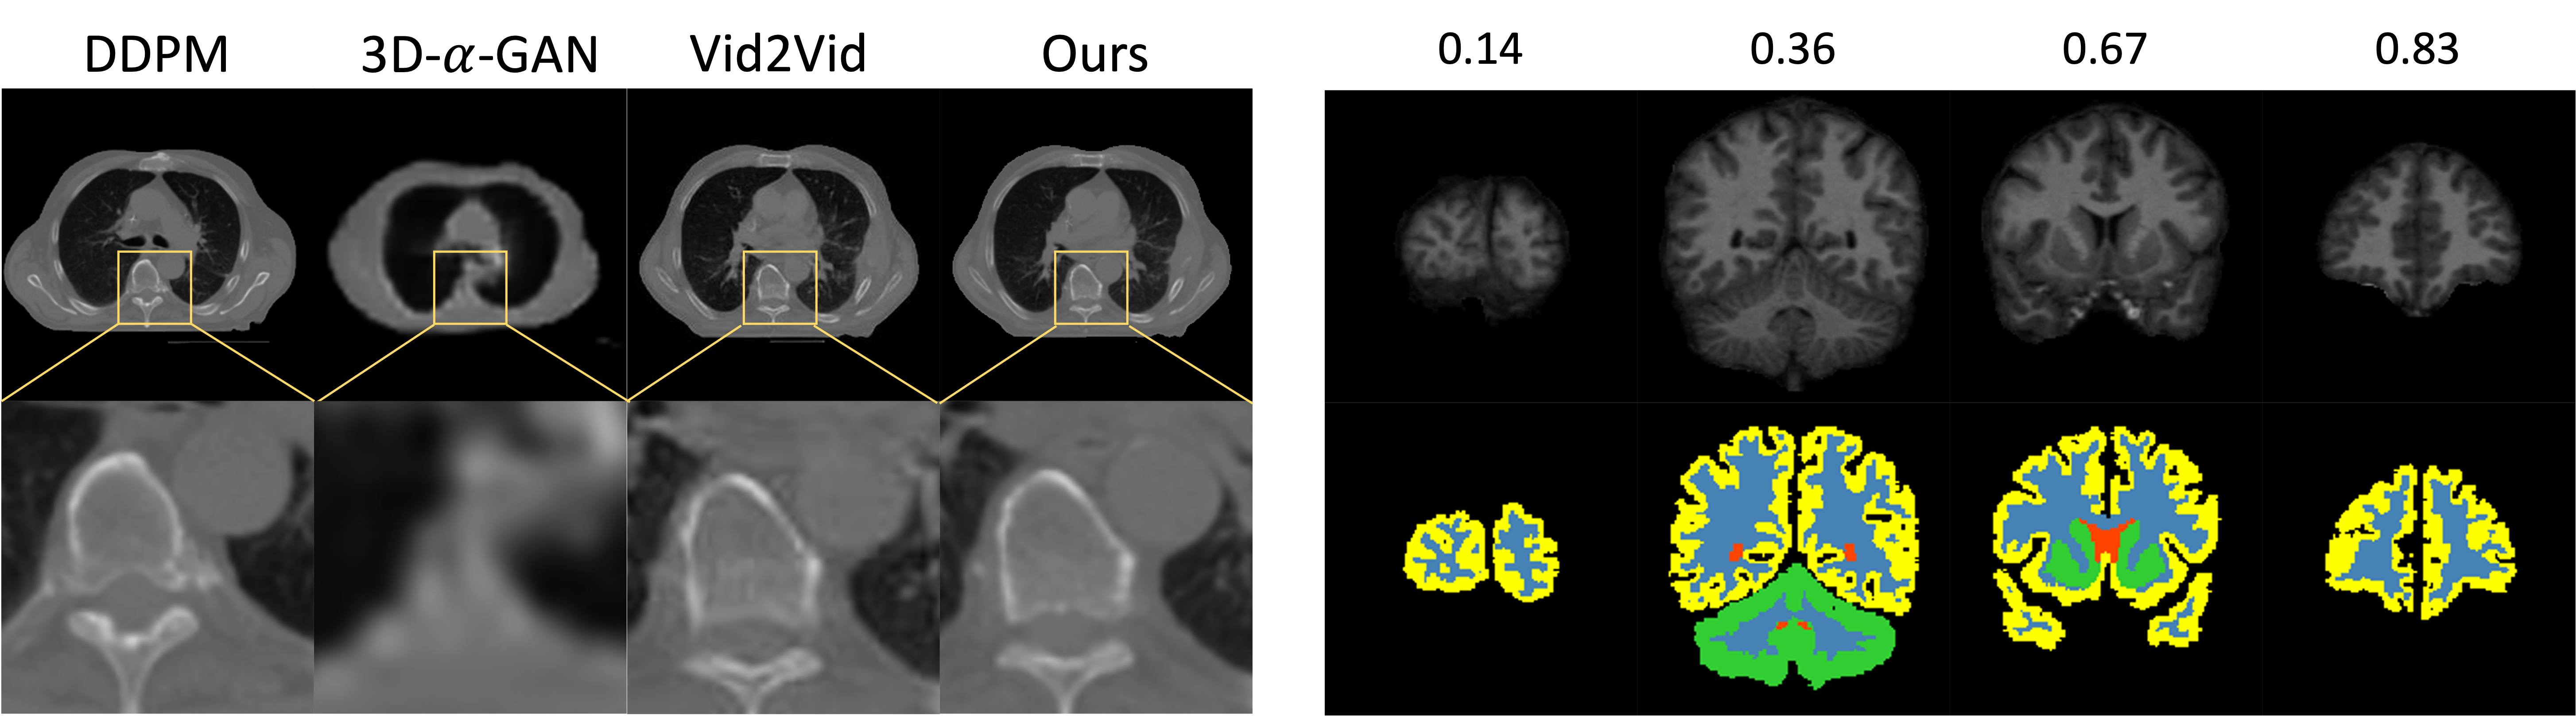

Refer to caption

Figure 4: Our proposed method produces more anatomically accurate images compared to 3D-α𝛼\alpha-WGAN and vid2vid, as demonstrated by the clearer organ boundaries and more realistic textures. Left: Qualitative comparison between different generative models. Right: Visualization of synthetic 3D brain MRI slices at different relative positions.